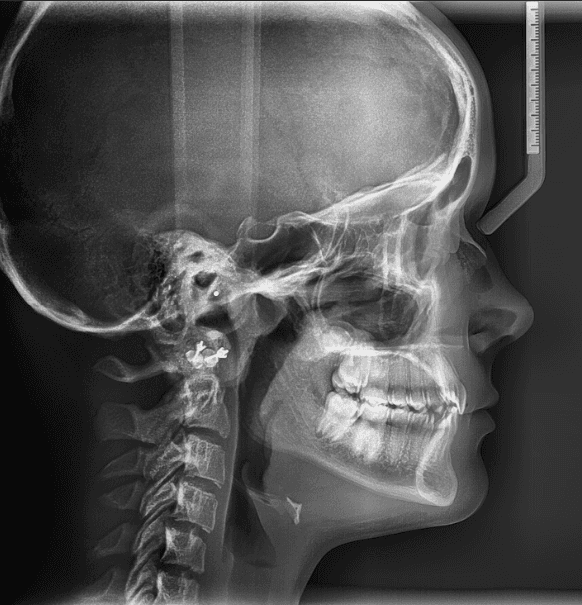

Adjuncts: Class II elastics, attachments, IPR

X-RAYS